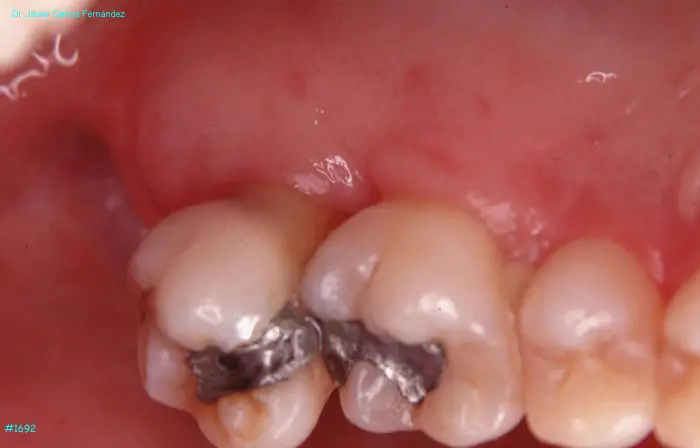

Atlas of Surgical Techniques in Periodontics. Chapter IV. Atlas de Técnicas Quirúrgica en Periodoncia

image 204